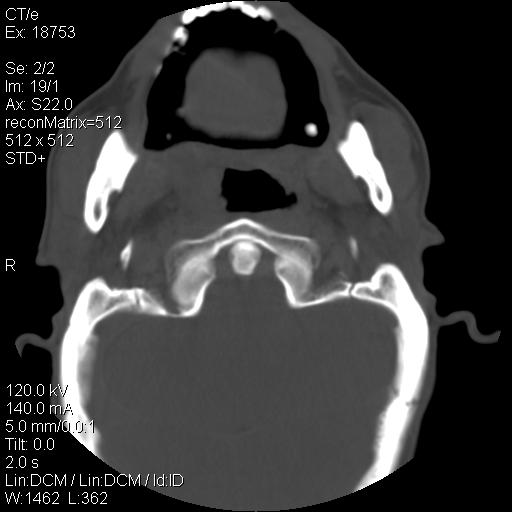

标题: CT21693:男 58岁 右侧咽部疼她2天余 PE:右侧扁桃体肿大 压痛 [打印本页]

标题: CT21693:男 58岁 右侧咽部疼她2天余 PE:右侧扁桃体肿大 压痛

右化脓性扁桃体炎症伴咽后壁脓肿形成.

以下是引用zjzjr在2009-8-19 21:07:00的发言:[br]右化脓性扁桃体炎症伴咽后壁脓肿形成.